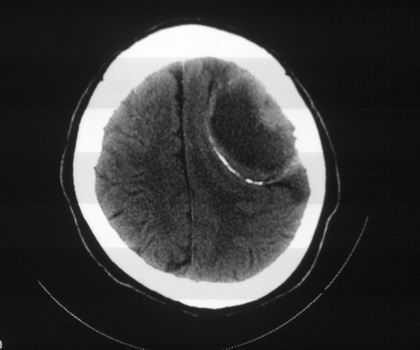

以下是引用影像孺子牛在2008-4-29 21:20:00的发言:[br]首先病变定位在脑外,根据ct密度及mri信号特征考虑慢性硬膜下血肿不连续环形钙化。

以下是引用周战梅在2008-4-29 23:12:00的发言:[br]脑外病变,蛛网膜下腔增宽,囊壁点状、环形钙化,增强扫描呈不均匀环状强化,考虑为囊性脑膜瘤可能性大,慢性脓肿、血肿机化、胆脂瘤不能除外。